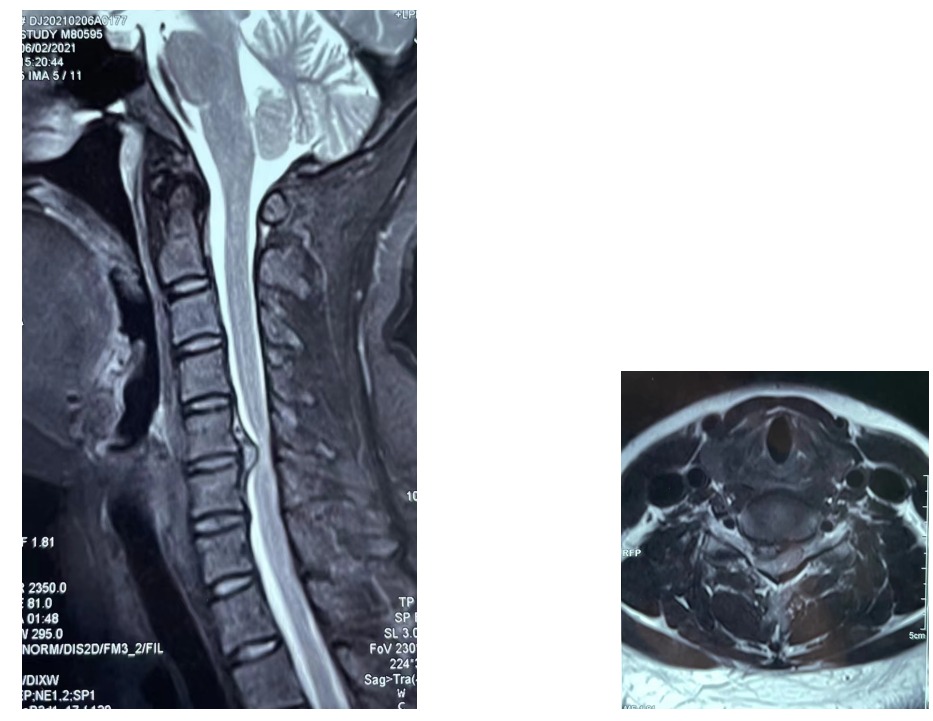

一 神经根型颈椎病病例资料

主诉: 右上肢酸痛麻木2月余

现病史:患者2月前无明显诱因出现右上肢酸痛麻木症状,休息后稍缓解,后症状间断反复,在当地医院给予“药物、针灸、理疗”等保守治疗,效果欠佳;自觉其症状逐渐加重,影响正常生活,今日为求进一步诊治来我院,门诊查颈椎MR提示:C5/6颈椎间盘偏右侧突出压迫脊髓。遂以“神经根型颈椎病”为诊断收住我科。 发病以来,神志清楚,精神尚可,饮食正常,睡眠一般,体力正常,大小便正常。

专科查体:颈椎前屈及左右侧屈活动受限,压颈试验阳性,右侧臂丛神经牵拉试验阳性,左侧肢体感觉、运动及肌力均正常。右侧躯干感觉轻度减退,右侧肢体肌张力增高,右上肢肌力IV级;右下肢肌力正常。双侧肱二头肌、肱三头肌腱反射(+++),桡骨膜反射(+++),右上肢Hoffmann征阳性,双下肢膝腱反射(+++),Babinski’s Sign征阴性L4/5棘间压痛、叩击痛,右下肢外侧放射痛,右足踇趾感觉减退,双下肢肌力V级,生理反射存在,病理反射未引出。直腿抬高试验及加强试验:左侧:阴性,右侧:40°(+),加强(+)。双侧“4”字试验及大腿滚动试验均(-)。双下肢未见明显肌肉萎缩。

影像学资料:

术前